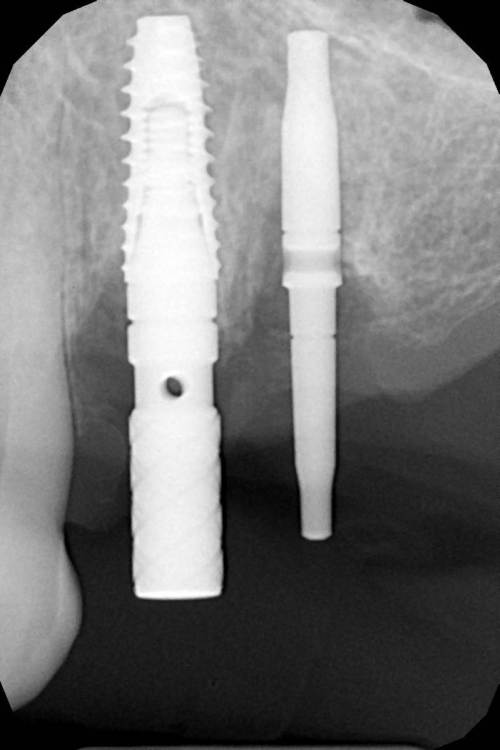

АнтонТЛТ Опубликовано 11 января, 2022 Поделиться Опубликовано 11 января, 2022 Что-то через чур близко Ссылка на комментарий

Женька Опубликовано 11 января, 2022 Автор Поделиться Опубликовано 11 января, 2022 @АнтонТЛТ я думаю это как раз тот снимок когда я ещё не поменял направление. Ведь на интраоральных фото нет излишней близости? Ссылка на комментарий

АнтонТЛТ Опубликовано 11 января, 2022 Поделиться Опубликовано 11 января, 2022 16 минут назад, Женька сказал: @АнтонТЛТ я думаю это как раз тот снимок когда я ещё не поменял направление. Ведь на интраоральных фото нет излишней близости? Т.е. там между имплантатами есть 3мм? Ссылка на комментарий

Женька Опубликовано 11 января, 2022 Автор Поделиться Опубликовано 11 января, 2022 @АнтонТЛТ 3х конечно наверное нет... Ссылка на комментарий

Irouil Опубликовано 11 января, 2022 Поделиться Опубликовано 11 января, 2022 Конечно наверное) Планирование и реализация сильно отличаются - фантомы винтов стоят в лунке 4-ки и дистальной стенке дунет 5-ки, а на практике - в дистальной стенке лунки 4-ки и в медиальной стенке лунки 5-ки Ссылка на комментарий

kramer Опубликовано 11 января, 2022 Поделиться Опубликовано 11 января, 2022 (изменено) 24 25 скорее всего хана придет, не сразу, так потом. Слишком уж близко. Я бы ставил в позиции 24 26 27 Изменено 11 января, 2022 пользователем kramer Ссылка на комментарий